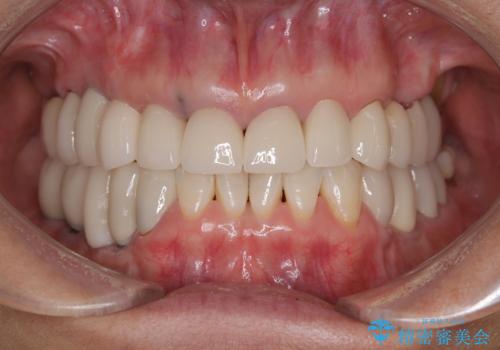

全顎的な治療後に、急遽ニューヨークへ転居されることとなったのですが、治療後から経過観察を行っていた右上犬歯が歯肉縁下に及ぶむし歯のため、クラウンが土台ごと外れてしまったとの連絡がありました。

他の部位にインプラント治療を行っていたことから、こちらの歯に対してもインプラントによる補綴治療を希望されたため、1泊での帰国時に抜歯、インプラント埋入、仮歯の装着を行い、数ヶ月後の帰国時にオールセラミッククラウンの型取りと装着を行う計画としました。

インプラント埋入時は1泊、補綴治療時には3週間ほど日本に滞在していただき、2回の渡航で無事に治療を終えることができました。